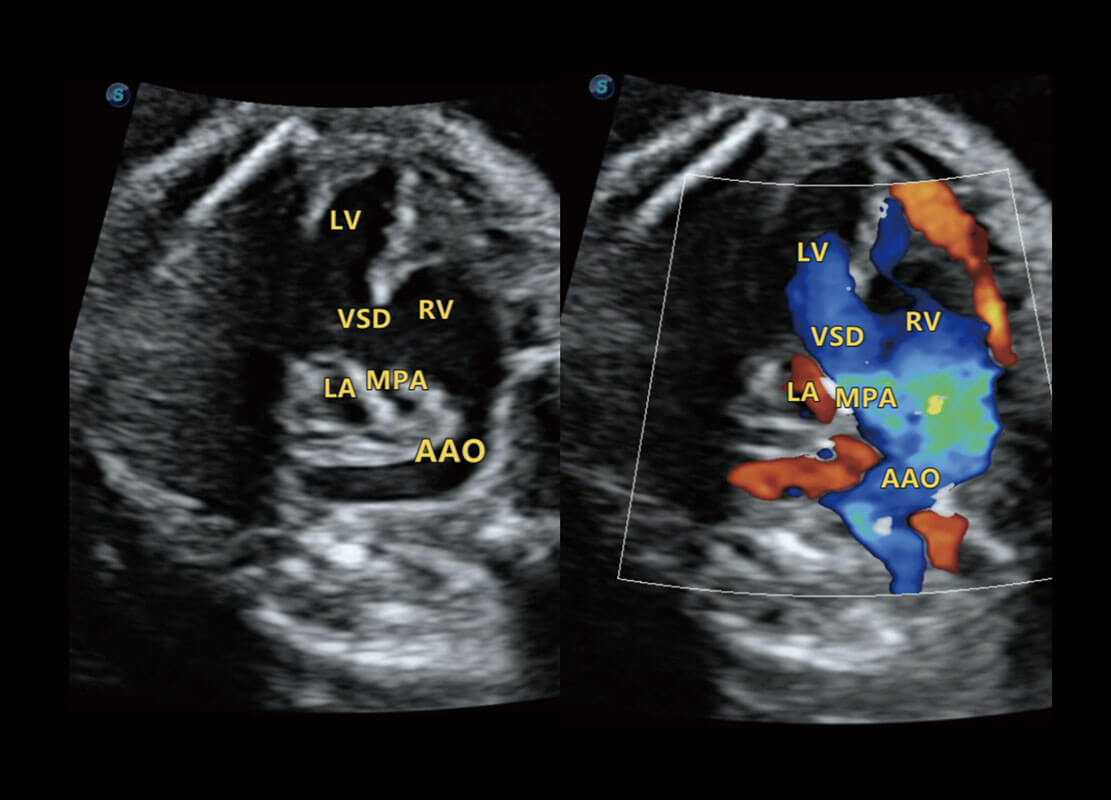

四腔心血流

右室双出口